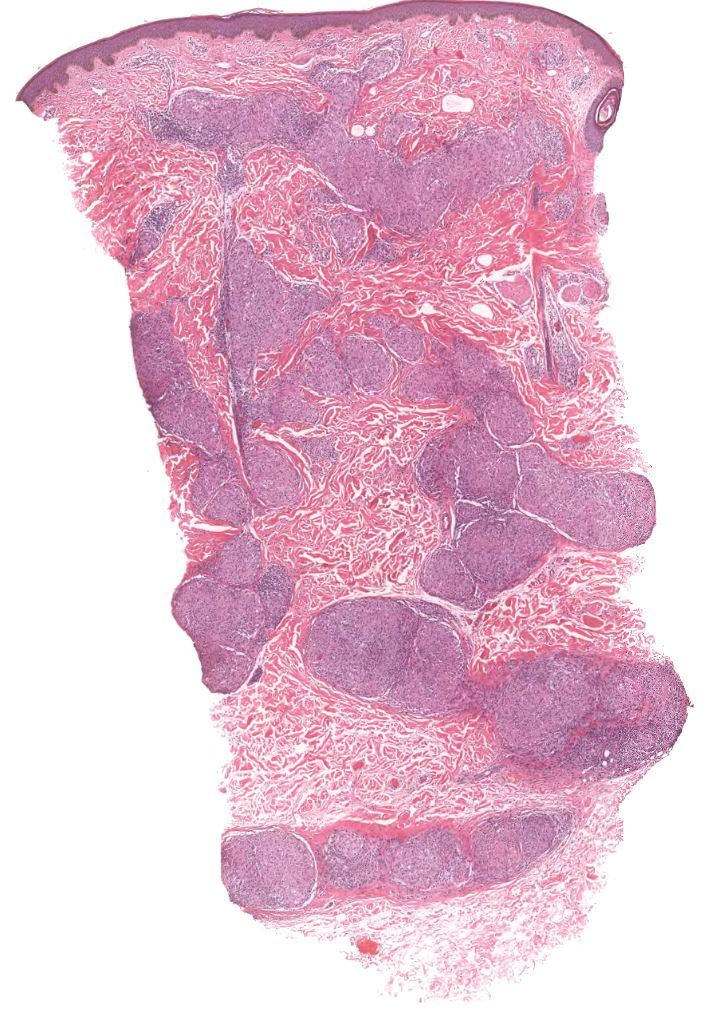

Rosai Dorfman

Fibrotic nodules showing light and dark areas

Sheets of histiocytes (light areas) with nodules of lymphoytes (dark areas)

Emperipolesis (intact cells, especially lymphocytes and plasma cells, passing through histiocytes)

S100 positive, CD1a negative, CD68 positive